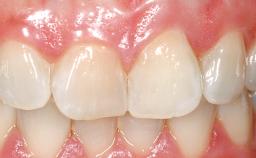

Late Placement of an Implant in a Maxillary Left Central Incisor Site

A 30-year-old female patient had lost tooth 21 and was referred to our clinic for consultation and treatment. Due to advanced apical infection, tooth 21 had been extracted two months earlier at another clinic and an acrylic-resin tooth had been bonded to the adjacent teeth. The patient desired implant treatment to avoid any damage to the adjacent natural teeth. While the patient had no history of any systemic disorder, she was a heavy smoker and exhibited medium to advanced periodontitis in the entire jaw. After the initial treatment to achieve a pocket probing depth of less than 4 mm and no bleeding on probing, a decrease in the height of the papillae mesial and distal to the extraction site and overall gingival recession were observed.

Prosthesis Type FDP

Retention Cemented, with meso-structure Cemented, with meso-structure

Provisional Implant-Supported Prosthesis Prosthodontic margin < 3 mm apical to mucosal margin Prosthodontic margin < 3 mm apical to mucosal margin